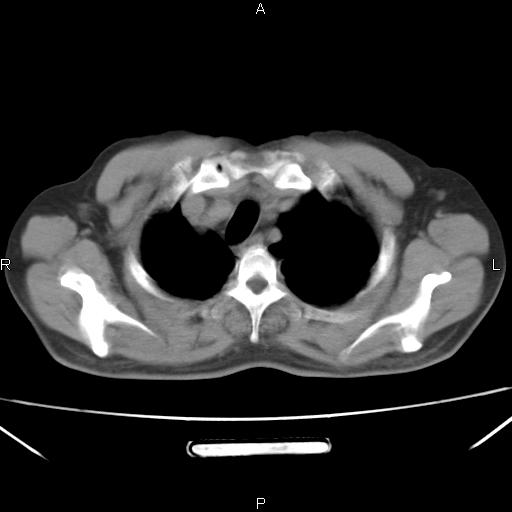

患者,男。50岁。近几日有咳嗽症状,无其他不适,既往病史无,考虑膈疝。请前辈们看看指导指导。

膈膨升,左下肺通气不良,膈肌好像还完整。

考虑左侧膈疝。

左侧膈疝。

符合隔膨升,膈肌较完整。